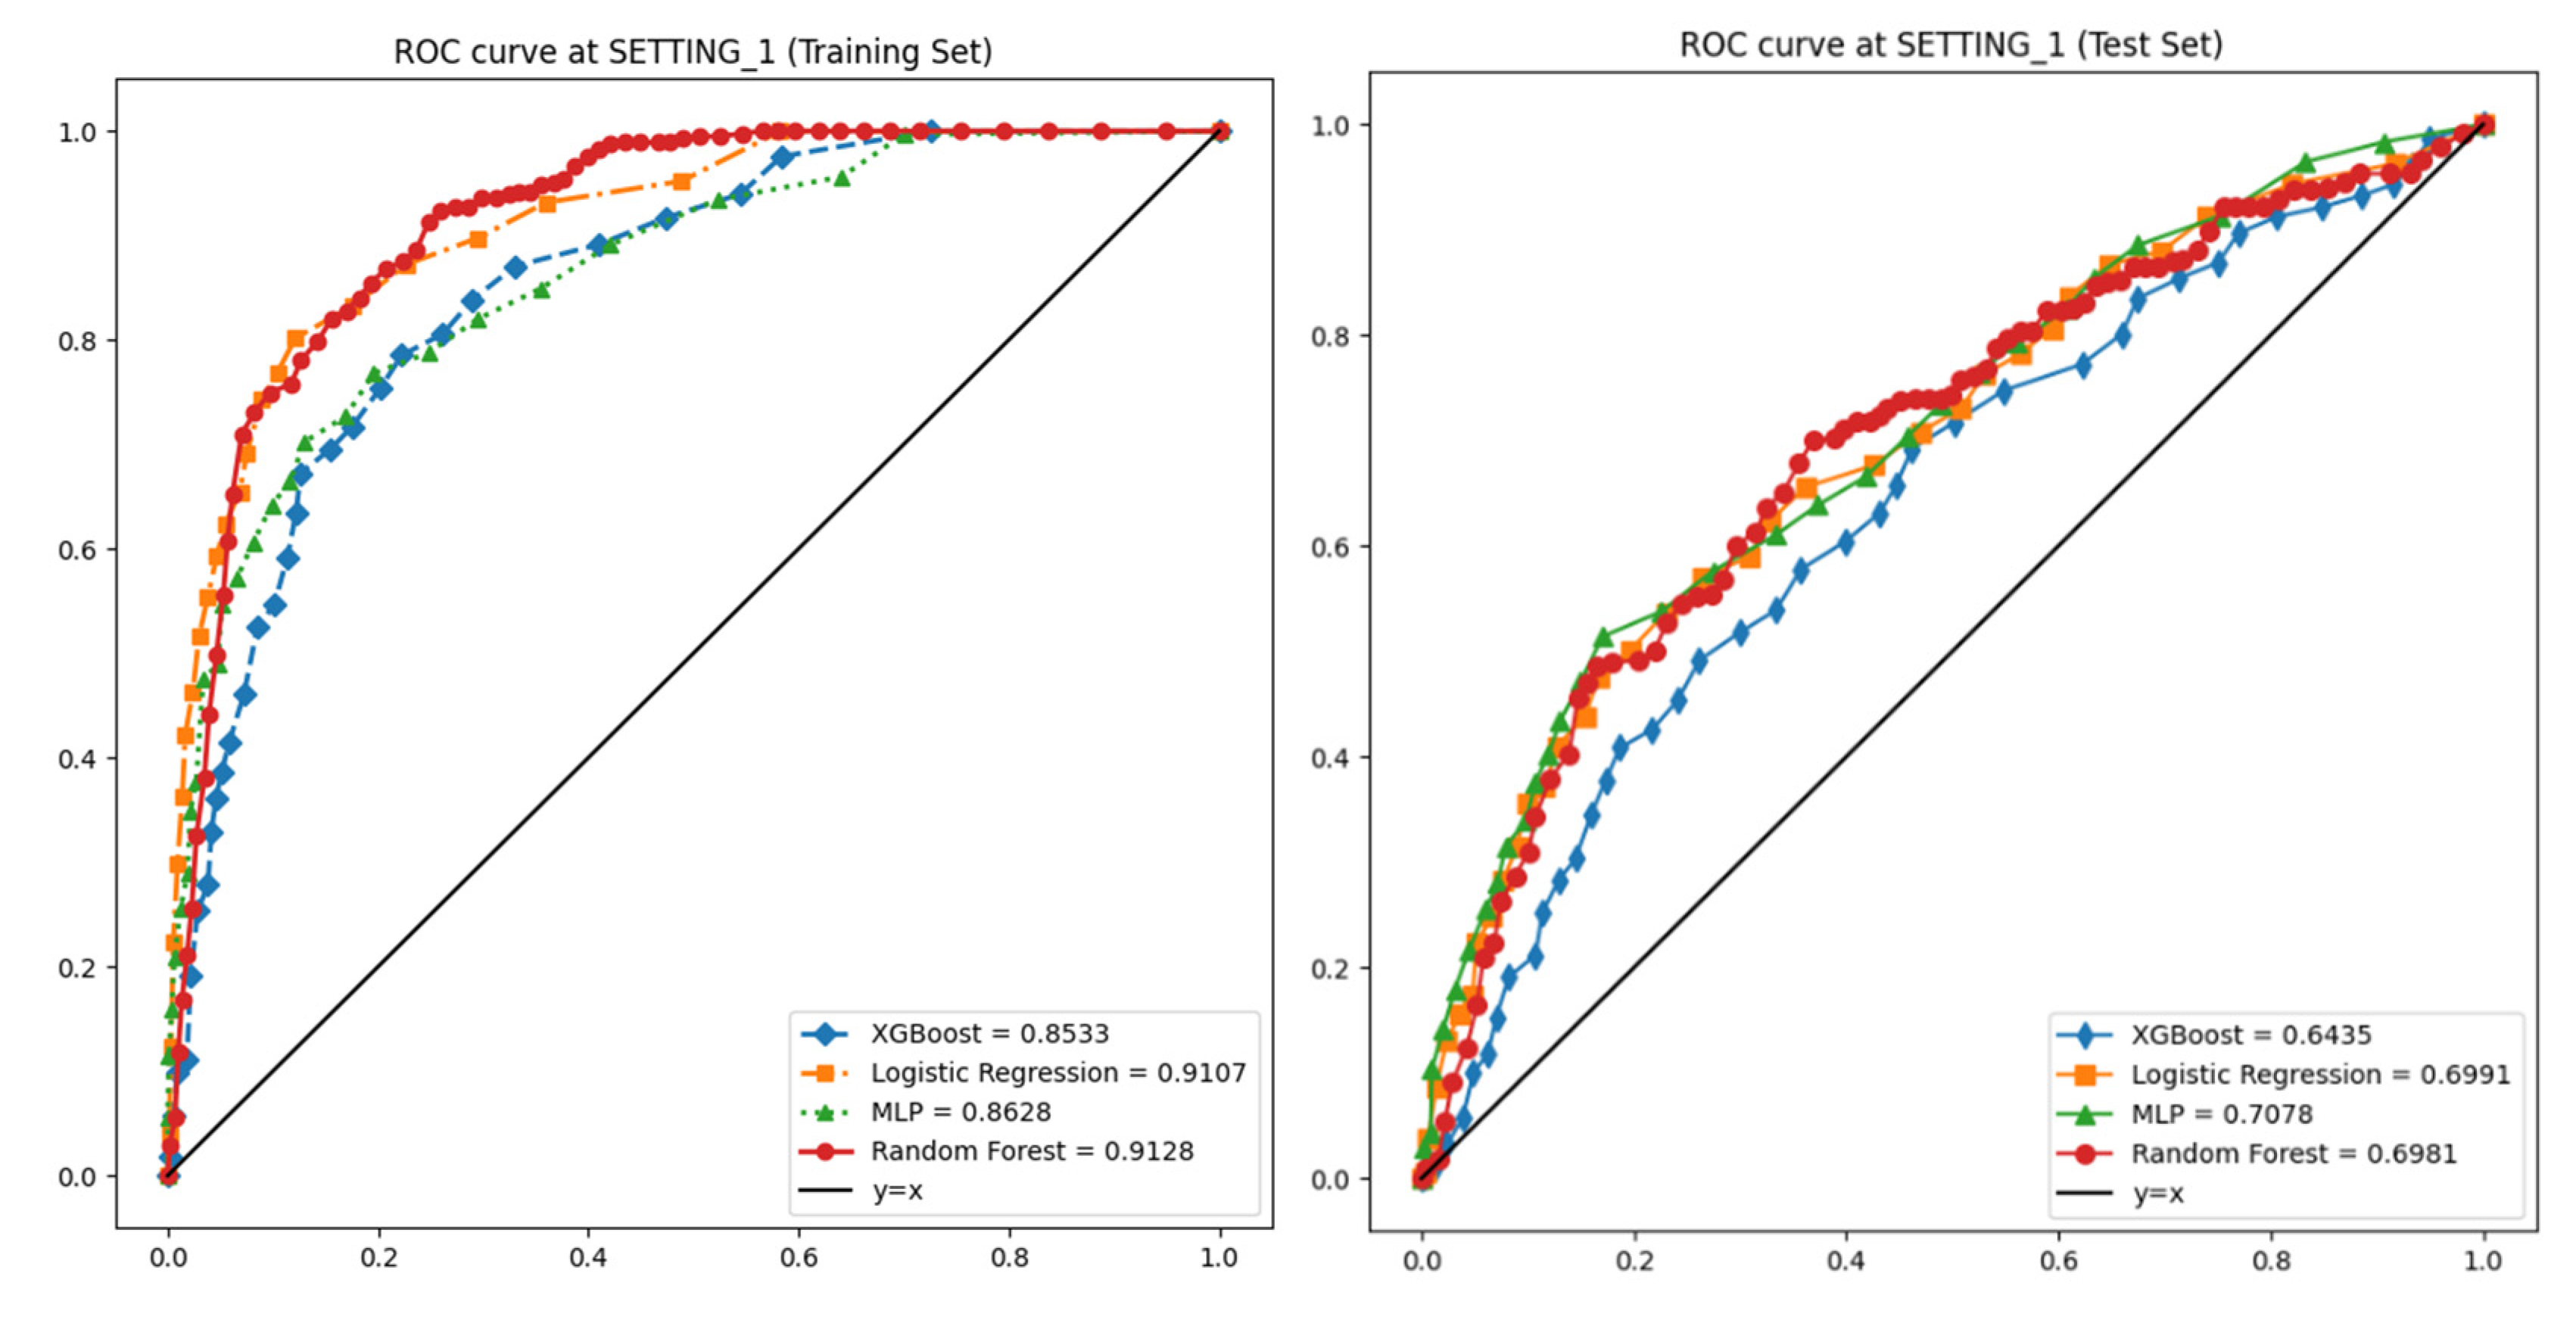

3.2. Performances of Machine Learning Models

| Datasets | Models | Accuracy | Specificity | Sensitivity | Precision | F1-Score | AUROC |

|---|---|---|---|---|---|---|---|

| SETTING_1 | Logistic Regression | 0.923 | 0.981 | 0.57 | 0.527 | 0.548 | 0.911 |

| Random Forest | 0.94 | 0.977 | 0.461 | 0.365 | 0.407 | 0.913 | |

| XGBoost | 0.935 | 0.969 | 0.397 | 0.296 | 0.339 | 0.853 | |

| Multi-Layer Perceptron | 0.891 | 0.991 | 0.488 | 0.553 | 0.519 | 0.863 | |

| Datasets | Models | Accuracy | Specificity | Sensitivity | Precision | F1-Score | AUROC |

|---|---|---|---|---|---|---|---|

| SETTING_1 | Logistic Regression | 0.757 | 0.957 | 0.143 | 0.527 | 0.223 | 0.699 |

| Random Forest | 0.871 | 0.958 | 0.185 | 0.365 | 0.244 | 0.698 | |

| XGBoost | 0.856 | 0.949 | 0.154 | 0.296 | 0.192 | 0.643 | |

| Multi-Layer Perceptron | 0.76 | 0.961 | 0.151 | 0.553 | 0.232 | 0.708 | |